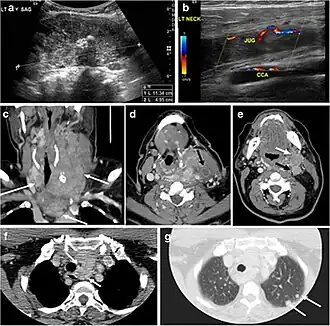

Fig. 16. Midline ectopic thyroid with Hashimoto's thyroiditis in a 49-year-old female patient. a Transverse greyscale ultrasound shows a 1.6 × 0.8 cm solid, well-defined, heterogeneous area (white arrow) in the midline, superior to the thyroid gland. It is iso-echogenic to the thyroid gland with no definite connection to the thyroid gland. b Transverse colour Doppler ultrasound shows significant increase in vascularity. c Axial enhanced neck CT scan at the level of thyroid cartilage demonstrates midline infrahyoid hyperdense soft tissue mass (white arrow) embedded within the strap muscle.[1]